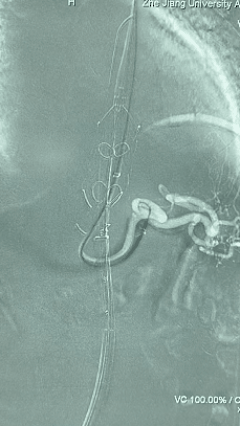

2. 左侧肱动脉入路,超选至降主动脉,更换8F-900mm长鞘,造影提示IV型胸腹主动脉瘤,累及双肾动脉。

4. 经长鞘导入导管后,超选入腹腔干动脉,送入先健覆膜支架10*80mm一枚,近端重叠内分支,远端重叠腹腔干动脉,并予以10mm球囊后扩,手推造影显影良好。

5. 撤出腹腔干导丝导管,经左肱动脉长鞘继续抓捕预置导丝将长鞘超选至另一侧内分支,后超选进肠系膜上动脉,沿导丝送入先健覆膜支架10*100mm一枚,近端重叠内分支,远端重叠于肠系膜上动脉,并予以10mm球囊后扩,手推造影显影良好。